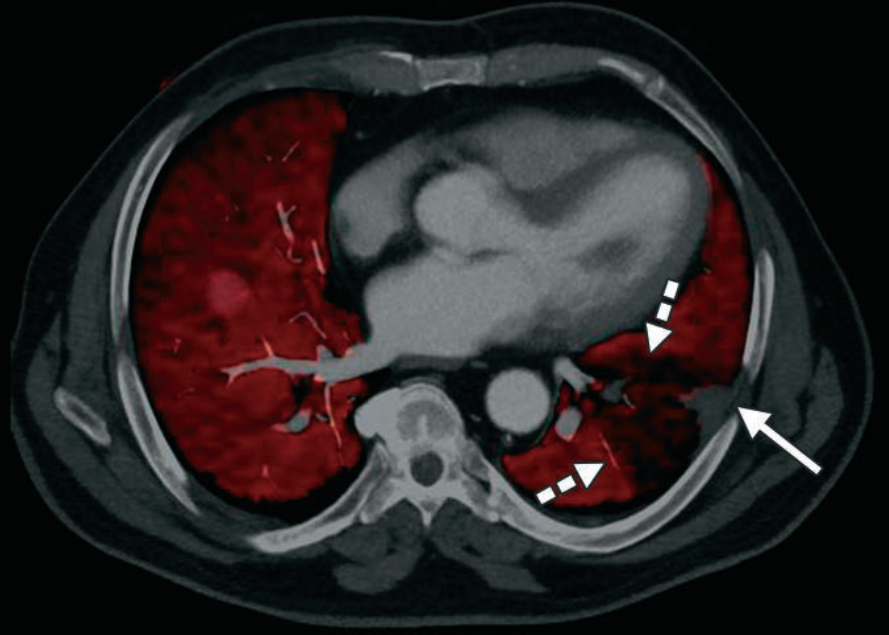

True vs. False Lumen in Acute Aortic Dissection

Look for the beak sign and larger caliber to ID the false; check the arch “wraparound” and calcification patterns for truth.